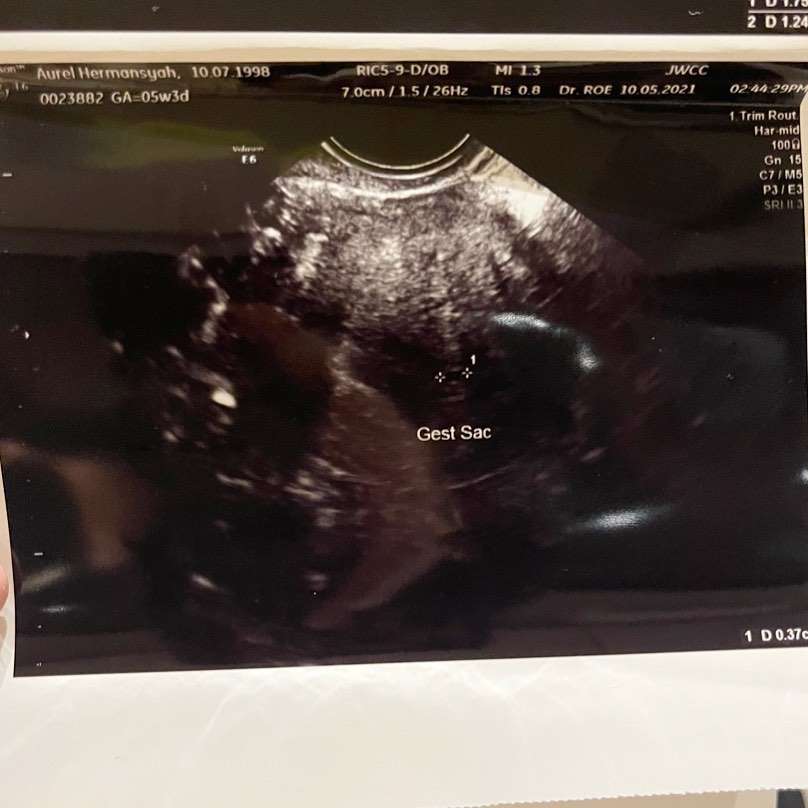

Dream - Pasangan YouTuber Atta Halilintar dan Aurel Hermansyah tengah berduka cita. Pasalnya, Aurel dikabarkan mengalami keguguran. Kabar duka ini disampaikan oleh Atta dan Aurel melalui akun Instagram masing-masing. Keduanya sama-sama mengunggah foto hasil USG dari janin yang dikandung oleh Aurel Hermansyah.

Sebelum keguguran, Aurel memang merasakan keganjilan pada kandungannya. Sebab dokter memang telah mengatakan kalau tubuh janin yang ada di kandungan Aurel sangat kecil. Padahal, di usia 5 minggu seharusnya usia kandungan tidak seperti demikian. Hal itulah yang kemudian membuat Aurel kerap menangis sedih.

“ Dokter tu bilang ini tu (janin) masih kecil banget. Padahal kalau dihitung dari masa haidnya seharusnya sudah lebih besar,” ungkap Aurel Hermansyah.

“ Nah, dari situlah mulai kepikiran terus..terus..kenapa ya. Sampai ke dokter kedua kalinya, agak membesar sedikit (janin), tapi tidak sama seperti orang lain (ukuran janin kecil),” imbuhnya.